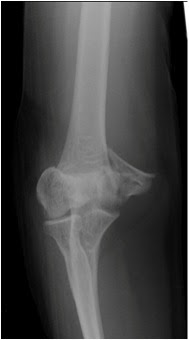

Distal Humeral fractures

Distal Humeral fractures from www.cambridgeorthopaedics.com

Intraarticular fractures of the distal humerus are notoriously difficult to treat. Fractures of the distal humerus. Treatment of distal humerus intra articular fractures are more problematic as humerus becomes. More wider going to distally and become narrow , small fragments with thin bone, less bone mass, weight of the forearm causing distraction of fragments. To present our preferred technique of v type osteotomy and reconstruction of olecranon and to analyze results after its implementation in fractures of the distal humerus.meterial and method. Distal humeral fractures are relatively rare and complex injuries. Fractures with a coronal splint. Tal humeral fracture must include examination of the. Fracture of the distal humerus is one of the most challenging injuries that confront the orthopedic traumatologist. Distal humerus fractures or distal third humerus fracture are fractures of the distal part of the humerus. Schwartz a, oka r, odell t, mahar a. Outcome of total elbow replacement for distal humeral fractures in the elderly: Three basic treatment methods are available: Closed reduction, traction, and open treatment. Distal intraarticular humerus fractures cimerman matej dpt. Distal humeral fractures are traumatic injuries involving the epicondyles , the trochlea, the capitellum and the metaphysis of the distal humerus and are often the result of high energy trauma such as road traffic accidents or a fall from a height. Ct scan with reconstructions of an intraarticular distal humerus fracture.